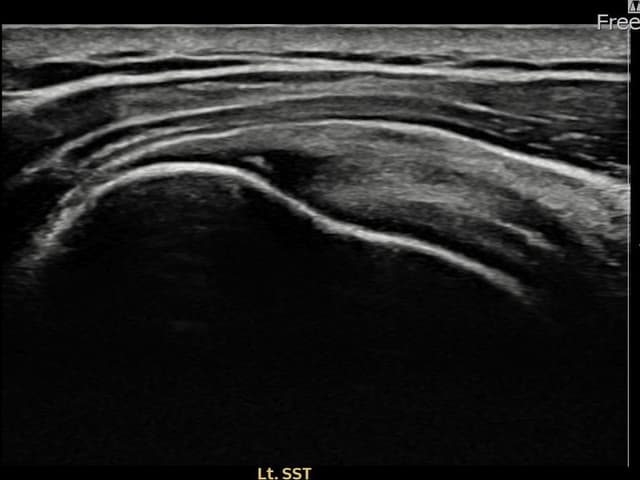

左侧 冈上肌腱 石灰化肌腱炎

16mm × 11mm